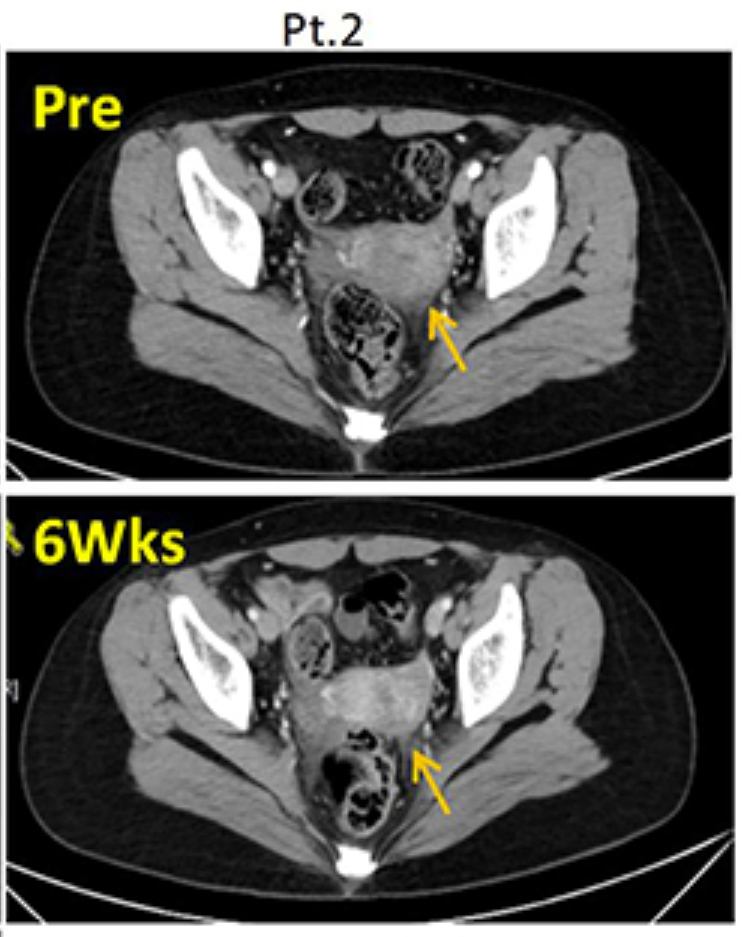

1、病情稳定(SD):患者在治疗后6周被评估为疾病稳定(SD)。在TIL输注前和治疗后6周时的CT扫描显示,目标病灶分别为5.9厘米和5.8厘米,显示病情稳定(详见下图)。

▲图源“Dovepress”,版权归原作者所有,如无意中侵犯了知识产权,请联系我们删除